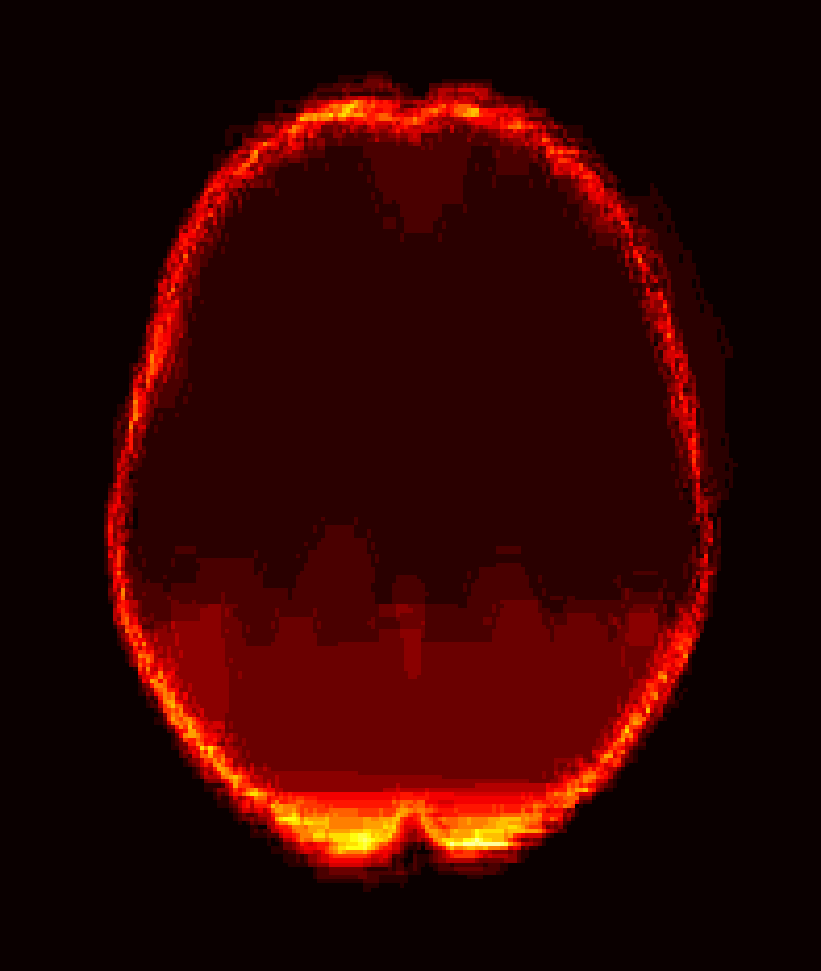

Fig. 1 shows example images from each dataset to illustrate image variability. IBSR and LPBA40 contain images from normal subjects and include large portions of the neck; BRATS has very low out-of-plane resolution; and the TBI dataset contains large pathologies and abnormal skulls.

Refer to caption

Figure 1: Illustration of image appearance variability on a selection of images from each (evaluation) database. From top to bottom: IBSR, LPBA40, BRATS and TBI.